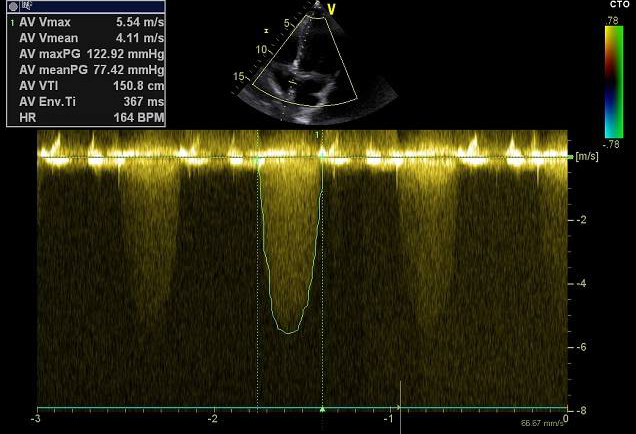

患者为67岁男性,反复晕厥两年,此次入院前2小时晕厥再发入院,入院诊断为:重度主动脉瓣狭窄合并轻度关闭不全,轻度二尖瓣反流,冠状动脉非梗阻性心肌梗死。

Type 1型二叶式主动脉瓣,瓣叶严重增厚,左右冠窦融合并形成钙化嵴,中度钙化,钙 化分布不均匀,最严重处为左右瓣叶融合嵴。主动脉瓣瓣环周长76.8mm,平均周长径24.3mm。

该患者瓣叶中度钙化,左右瓣叶钙化融合嵴较为坚硬,球囊打开难度较高,预估存在植入假体瓣膜形变、根部损伤风险,钙化融合嵴增加瓣周漏风险。同时瓣叶严重纤维增厚,存在人工瓣膜向下位移,有瓣中瓣治疗可能。冠脉高度可,根据瓣叶长度、瓦氏窦宽度预估右冠风险较小,左冠存在一定堵塞风险。

经过团队严谨的评估及充分的讨论,使用右侧股动脉为主入路,左侧辅助入路。预估跨瓣角度为LAO 6°,CRA 5°左右。20mm球囊预扩张。预装载TaurusOne®AV26瓣膜。推荐释放角度LAO 20°,CAU 15°(右窦中心位),偏高位释放(瓣环下0-2mm)。

术前导管测量压差120mmHg;术后导管测量压差8mmHg